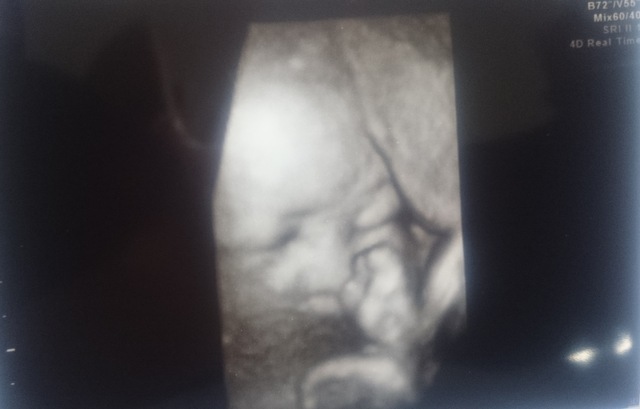

32週6日(32w6d・男の子)|みい(^-^) さん(25歳)

エコー写真撮影時のエピソード:

なかなかお顔を見せてくれず、やっと見えたお顔は頬杖をついた不機嫌?!な表情で、思わず笑ってしまったのを覚えています。産まれてからも色んな表情を見せてくれる我が子の成長をこれからも見守っていきたいです。